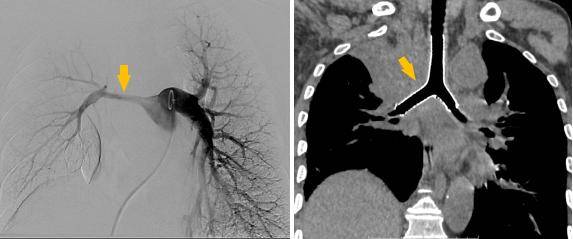

同期置入支架后狭窄明显改善